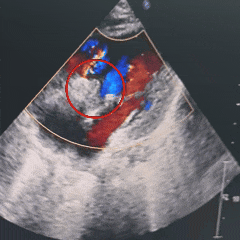

右盘展开后,超声下可见双盘骑跨于室间隔两侧,封堵器呈现“长哑铃”型

锁定后超声下可见封堵器呈“工”字型,盘面平整,贴合良好

释放后超声评估

超声四腔心及主动脉短轴切面观察封堵器形态良好,无残余分流,盘面平整,无周围瓣膜影响